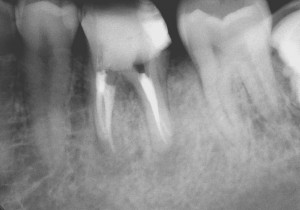

今回の患者様は、もうかれこれ10年の長いお付き合いの患者様です。来院のきっかけは、むし歯の治療でしたが、レントゲン写真から以前の神経を取った治療を行ったところに新たな病気が出来ていました。患者様の希望もあり、根管治療とその後の被せ物の治療も行いました。

約10年前のその当時を思い出してみると、私はマイクロスコープを使った根管治療を始めたばかりの頃だったと思います。いろいろなセミナーに通い、技術を習得していました。

その習得したばかりの技術を用いして何とかこの歯を保存できないかとがんばっていたことと思われます。

現在と比べると、使用している器具や材料では違いはありますが、治療において守るべき基本的なところは変わっておらず、基本に忠実な治療をしたのではないでしょうか。